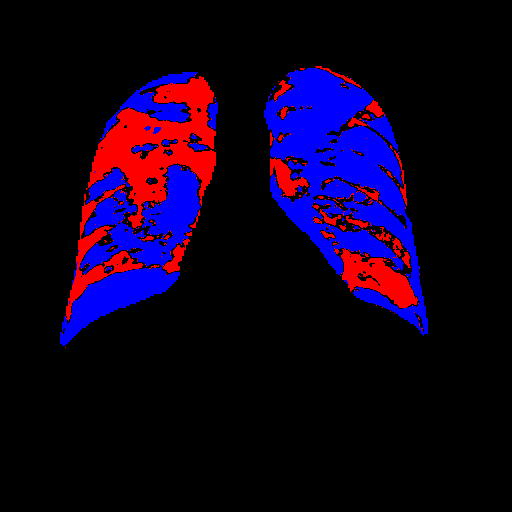

Side-by-side inspection of the generated healthy counterfactuals (as per fig. 2) suggests that, as required, only minimal perturbation is made to the original image with respect to healthy pixels -i.e. localized image sites without structural medical defects. (In the top row, the medical structural defect in the original image is due to a lung opacity, and characterized via a relatively complex interaction between the imaging modality and subject manifesting as ‘gaps’ in the corresponding portions of the lung scan). The healthy/non-healthy discrepancy maps in all of these cases are obtained via masked subtraction of the original image from the generated image (the ground truth segmentation masks correspond to the broad area of interest –i.e. the complete lung). The generated healthy tissue is thus a subset of the mask and is shown in the final column of fig. 2 for the respective cases.

In the context of a VANT-GAN[20]-based approach, this highlighted material constitutes the diagnostic counterfactual visual attribution, i.e. the selection of material relevant to the diagnosis of the unhealthy condition. Healthy counterfactual generation was performed for the complete datasets in the three unhealthy classes, i.e Lung opacity, Viral Pneumonia and COVID, examples of which are given in fig. 3 for the three classes (all of the generated healthy counterfactuals from this experiment can be found on https://huggingface.co/ammaradeel/diffusionVA). Visual inspection indicates that the generated counterfactuals are, in general, visually plausible with minimal perturbation made to the unhealthy image overall. Moreover, the healthy counterpart generation does not appear to unnecessarily affect aspects of the images unrelated to the medical condition, the model selectively making changes to the unhealthy regions in a structurally plausible manner, e.g. generating missing portions of the lung without generating extraneous lung material where it would be expected to normally exist (e.g. in the abdominal cavity).